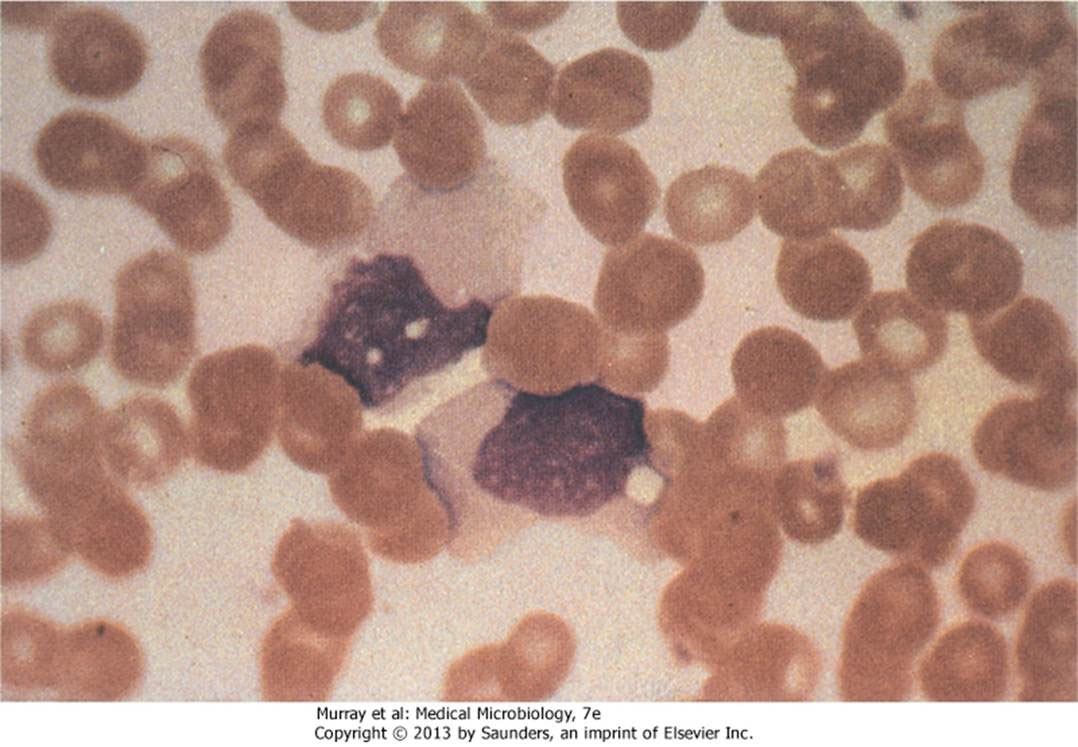

- Downey cell (Atypical lymphocytes)

- T cell 受 Heterophile Ab 刺激產生

- 具有更嗜鹼(深染)且空泡狀的細胞質

- 細胞核呈現腎形或葉形

- 邊緣因周圍紅血球作用而成鋸齒狀